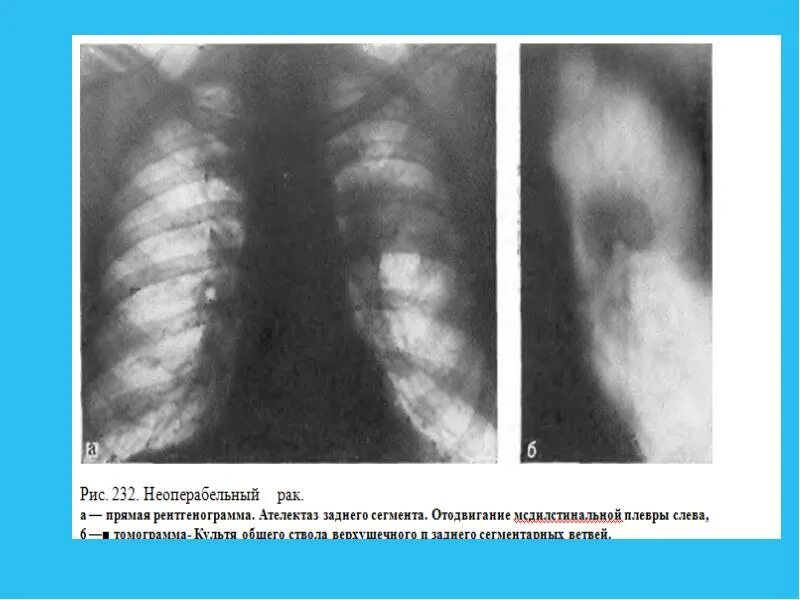

Рак неоперабельный 4 стадия